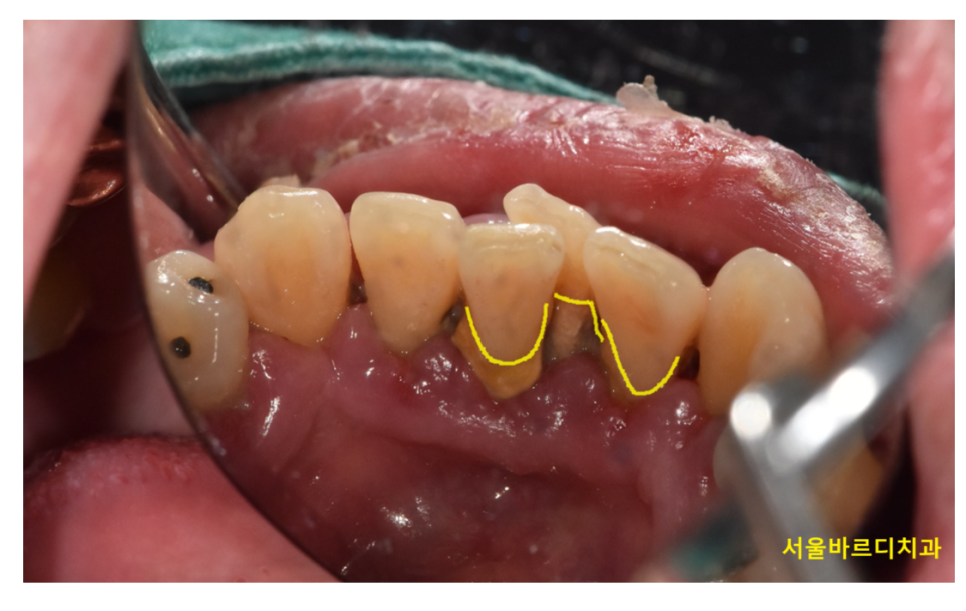

잇몸에 치석이 많거나 염증이 오래 있었던 경우,

치석을 제거하게 되면

치석으로 덮여있던 치아가

갑자기 외부로 노출되면서 시리게됩니다.

250131 치석으로 덮인 치아들